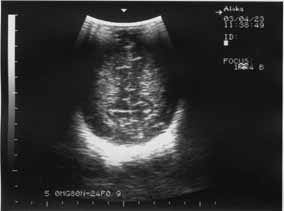

Кроме того, ишемический некроз проявляется повышением эхогенности обычно в острой фазе. В подострой и хронической фазах ведущую роль в диагностике играют неоднородность структуры, а также наличие участков с различной эхогенностью, в том числе кист. ПВЛ в подавляющем числе наблюдений является двусторонним процессом (рис. 1,2).

Рис. 1 Новорожденная Б 11 суток, СГ – 29 недель, ПВЛ III-IV степени на фоне повышенной эхогенности – мелкие анэхогенные образования (формирование кист). | Рис. 2. 10 суток, СГ – 30 недель, ПВЛ III степени, гиперэхогенность в перивентрикулярном пространстве (до образования кист). |

Эхографическое выявление острой фазы ПВЛ в первые сутки жизни может быть затруднительным. Это обстоятельство диктует необходимость динамического эхографического наблюдения за недоношенными детьми независимо от наличия или отсутствия у них морфологической картины поражения ЦНС в первые трое или даже семь суток жизни. С момента начала некротического процесса в веществе мозга до образования кисты обычно проходит 10-14 дней (рис.1,2). Во всех случаях перивентрикулярный некроз со временем приводит к пассивной внутренней гидроцефалии, которая может развиться через 2-3 недели после рождения.